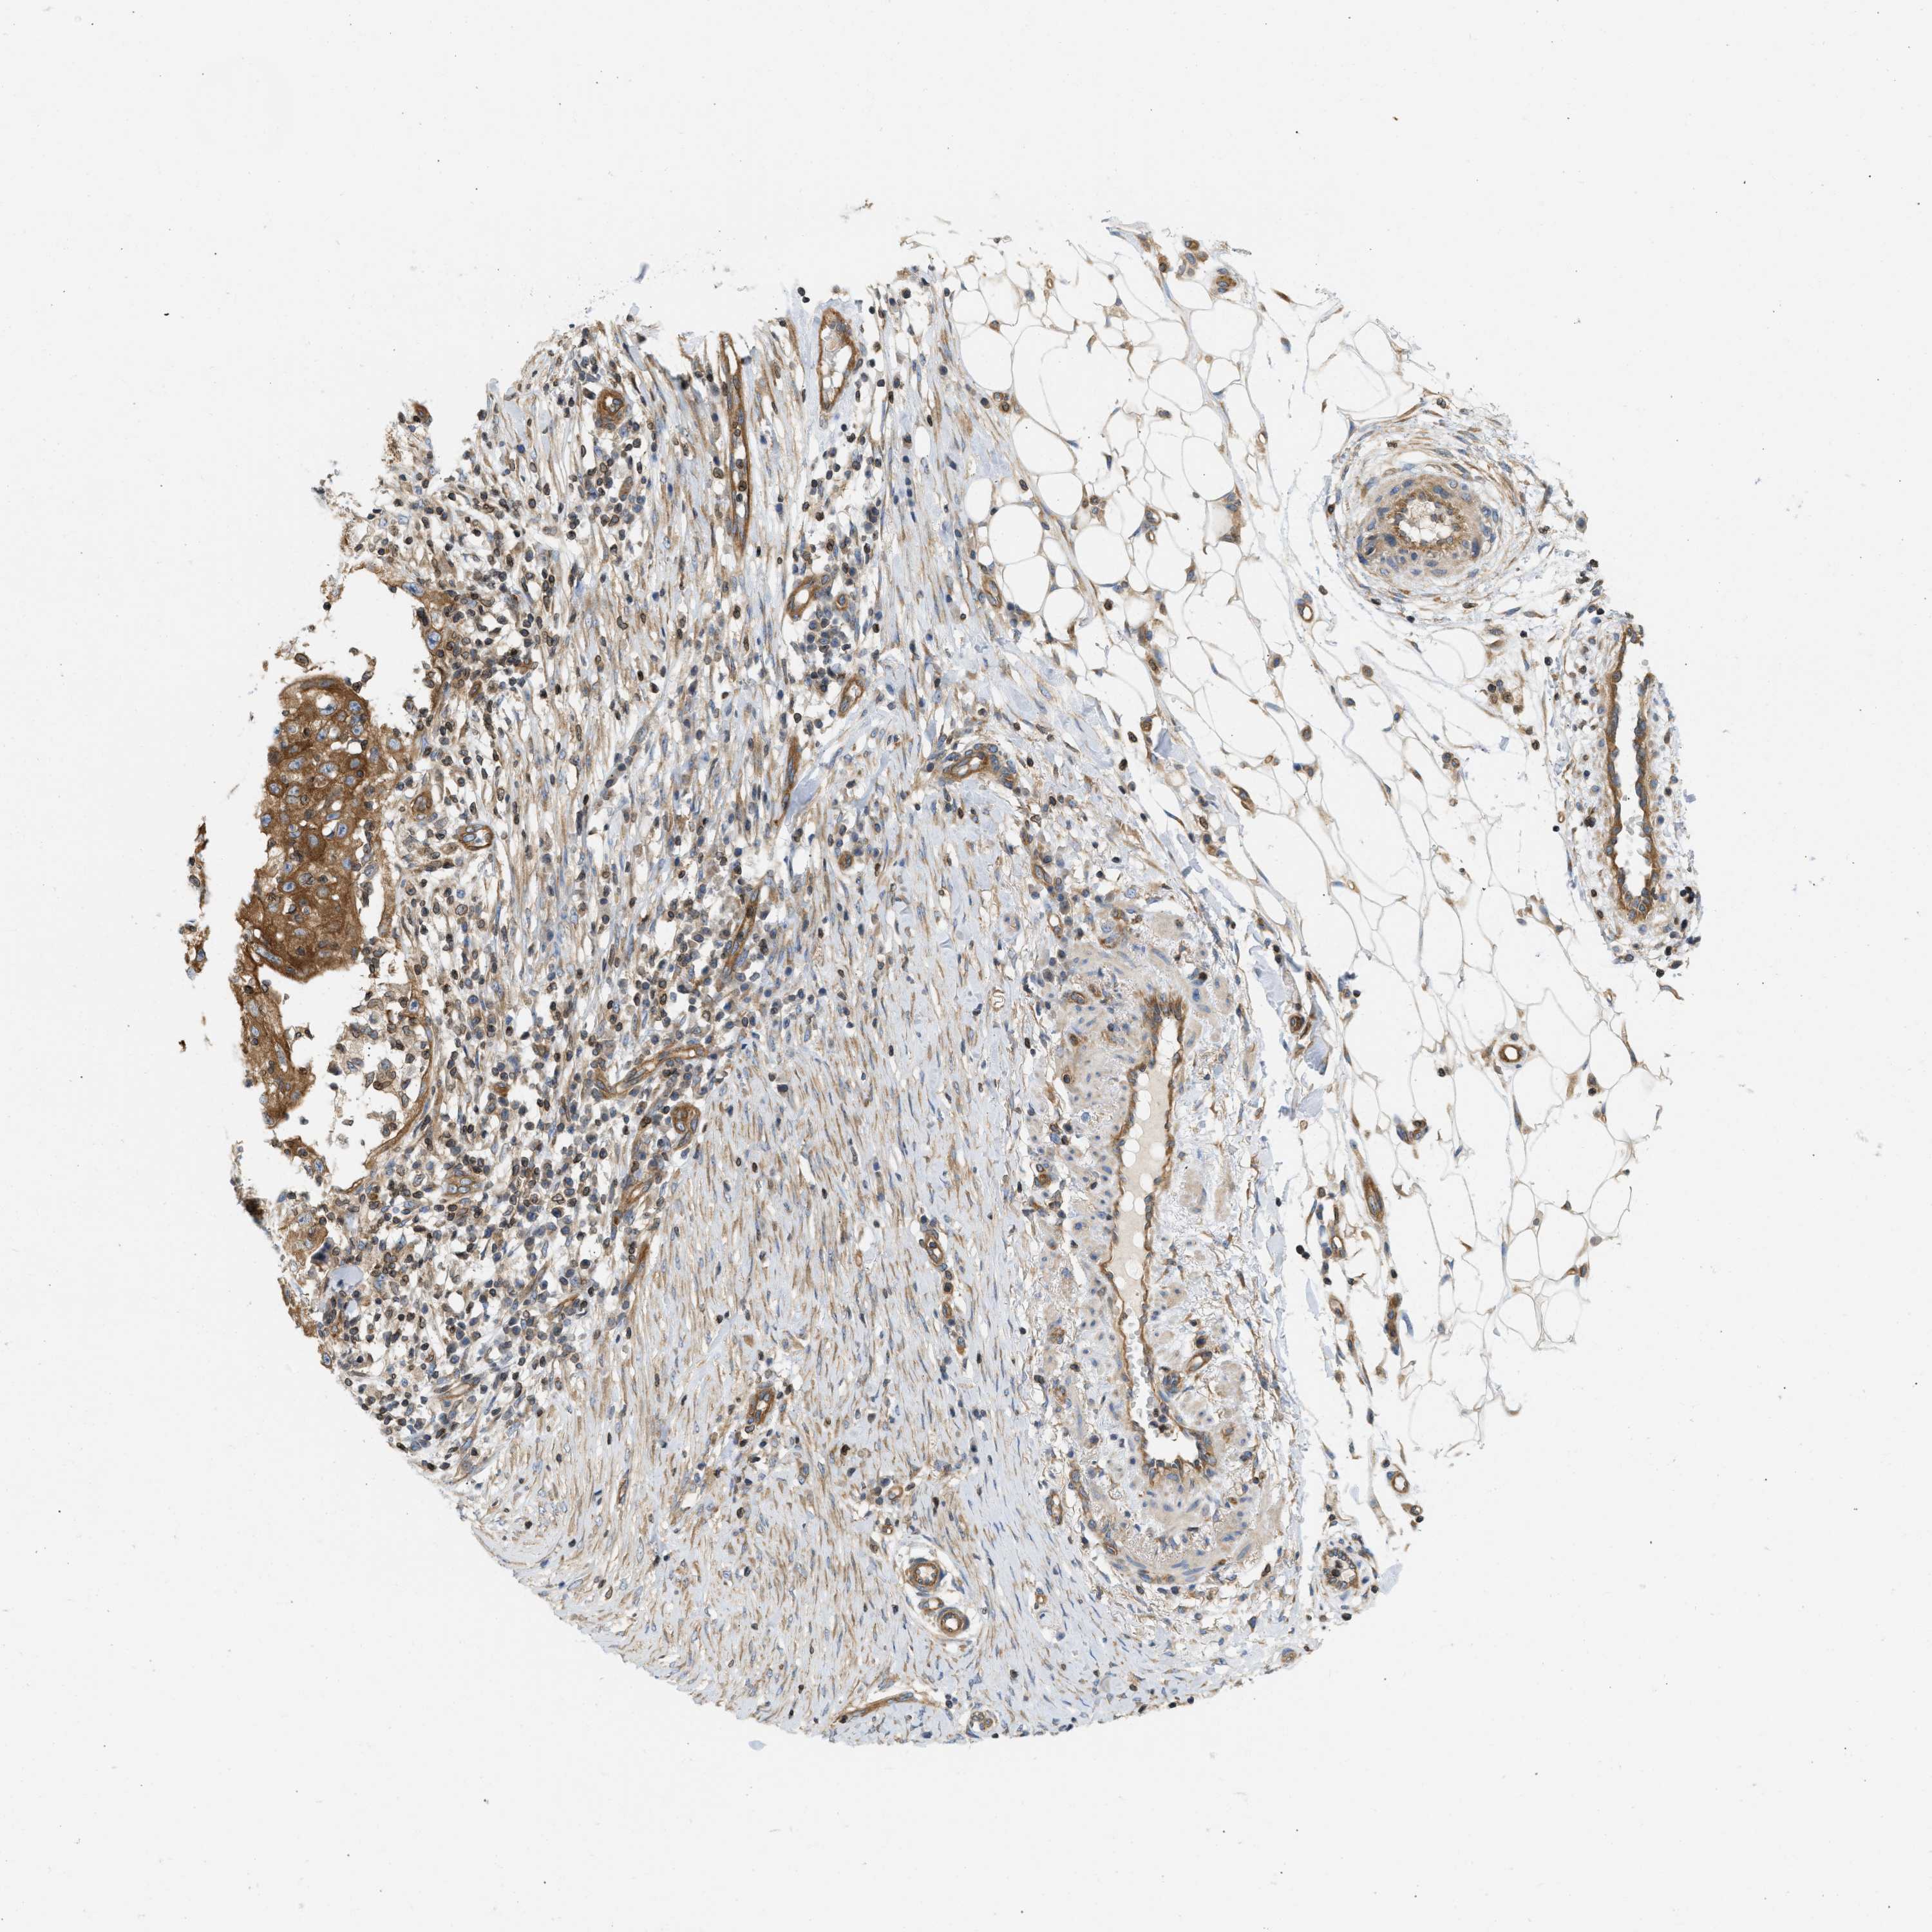

SKIN CANCER - Protein expressioni

A mouse-over function shows sample information and annotation data. Click on an image to view it in a full screen mode. Samples can be filtered based on level of antibody staining by selecting one or several of the following categories: high, medium, low and not detected. The assay and annotation is described here.

Antibody stainingi

Antibody staining in the annotated cell types in the current human tissue is reported as not detected, low, medium, or high, based on conventional immunohistochemistry profiling in selected tissues. This score is based on the combination of the staining intensity and fraction of stained cells.

Each image is clickable and will lead to virtual microscopy that enables deeper exploration of all samples and also displays staining intensity scores, fraction scores and subcellular localization as well as patient and tissue information for each sample.

Antibody HPA017286

Staining

High

Medium

Low

Not detected

Intensity

Strong

Moderate

Weak

Negative

Quantity

>75%

75%-25%

<25%

None

Location

Nuclear

Cytoplasmic/membranous

Cytoplasmic/membranous,nuclear

Squamous cell carcinoma in situ, NOS

Squamous cell carcinoma, NOS

Squamous cell carcinoma, metastatic, NOS

Basal cell carcinoma

Adnexal tumor, benign